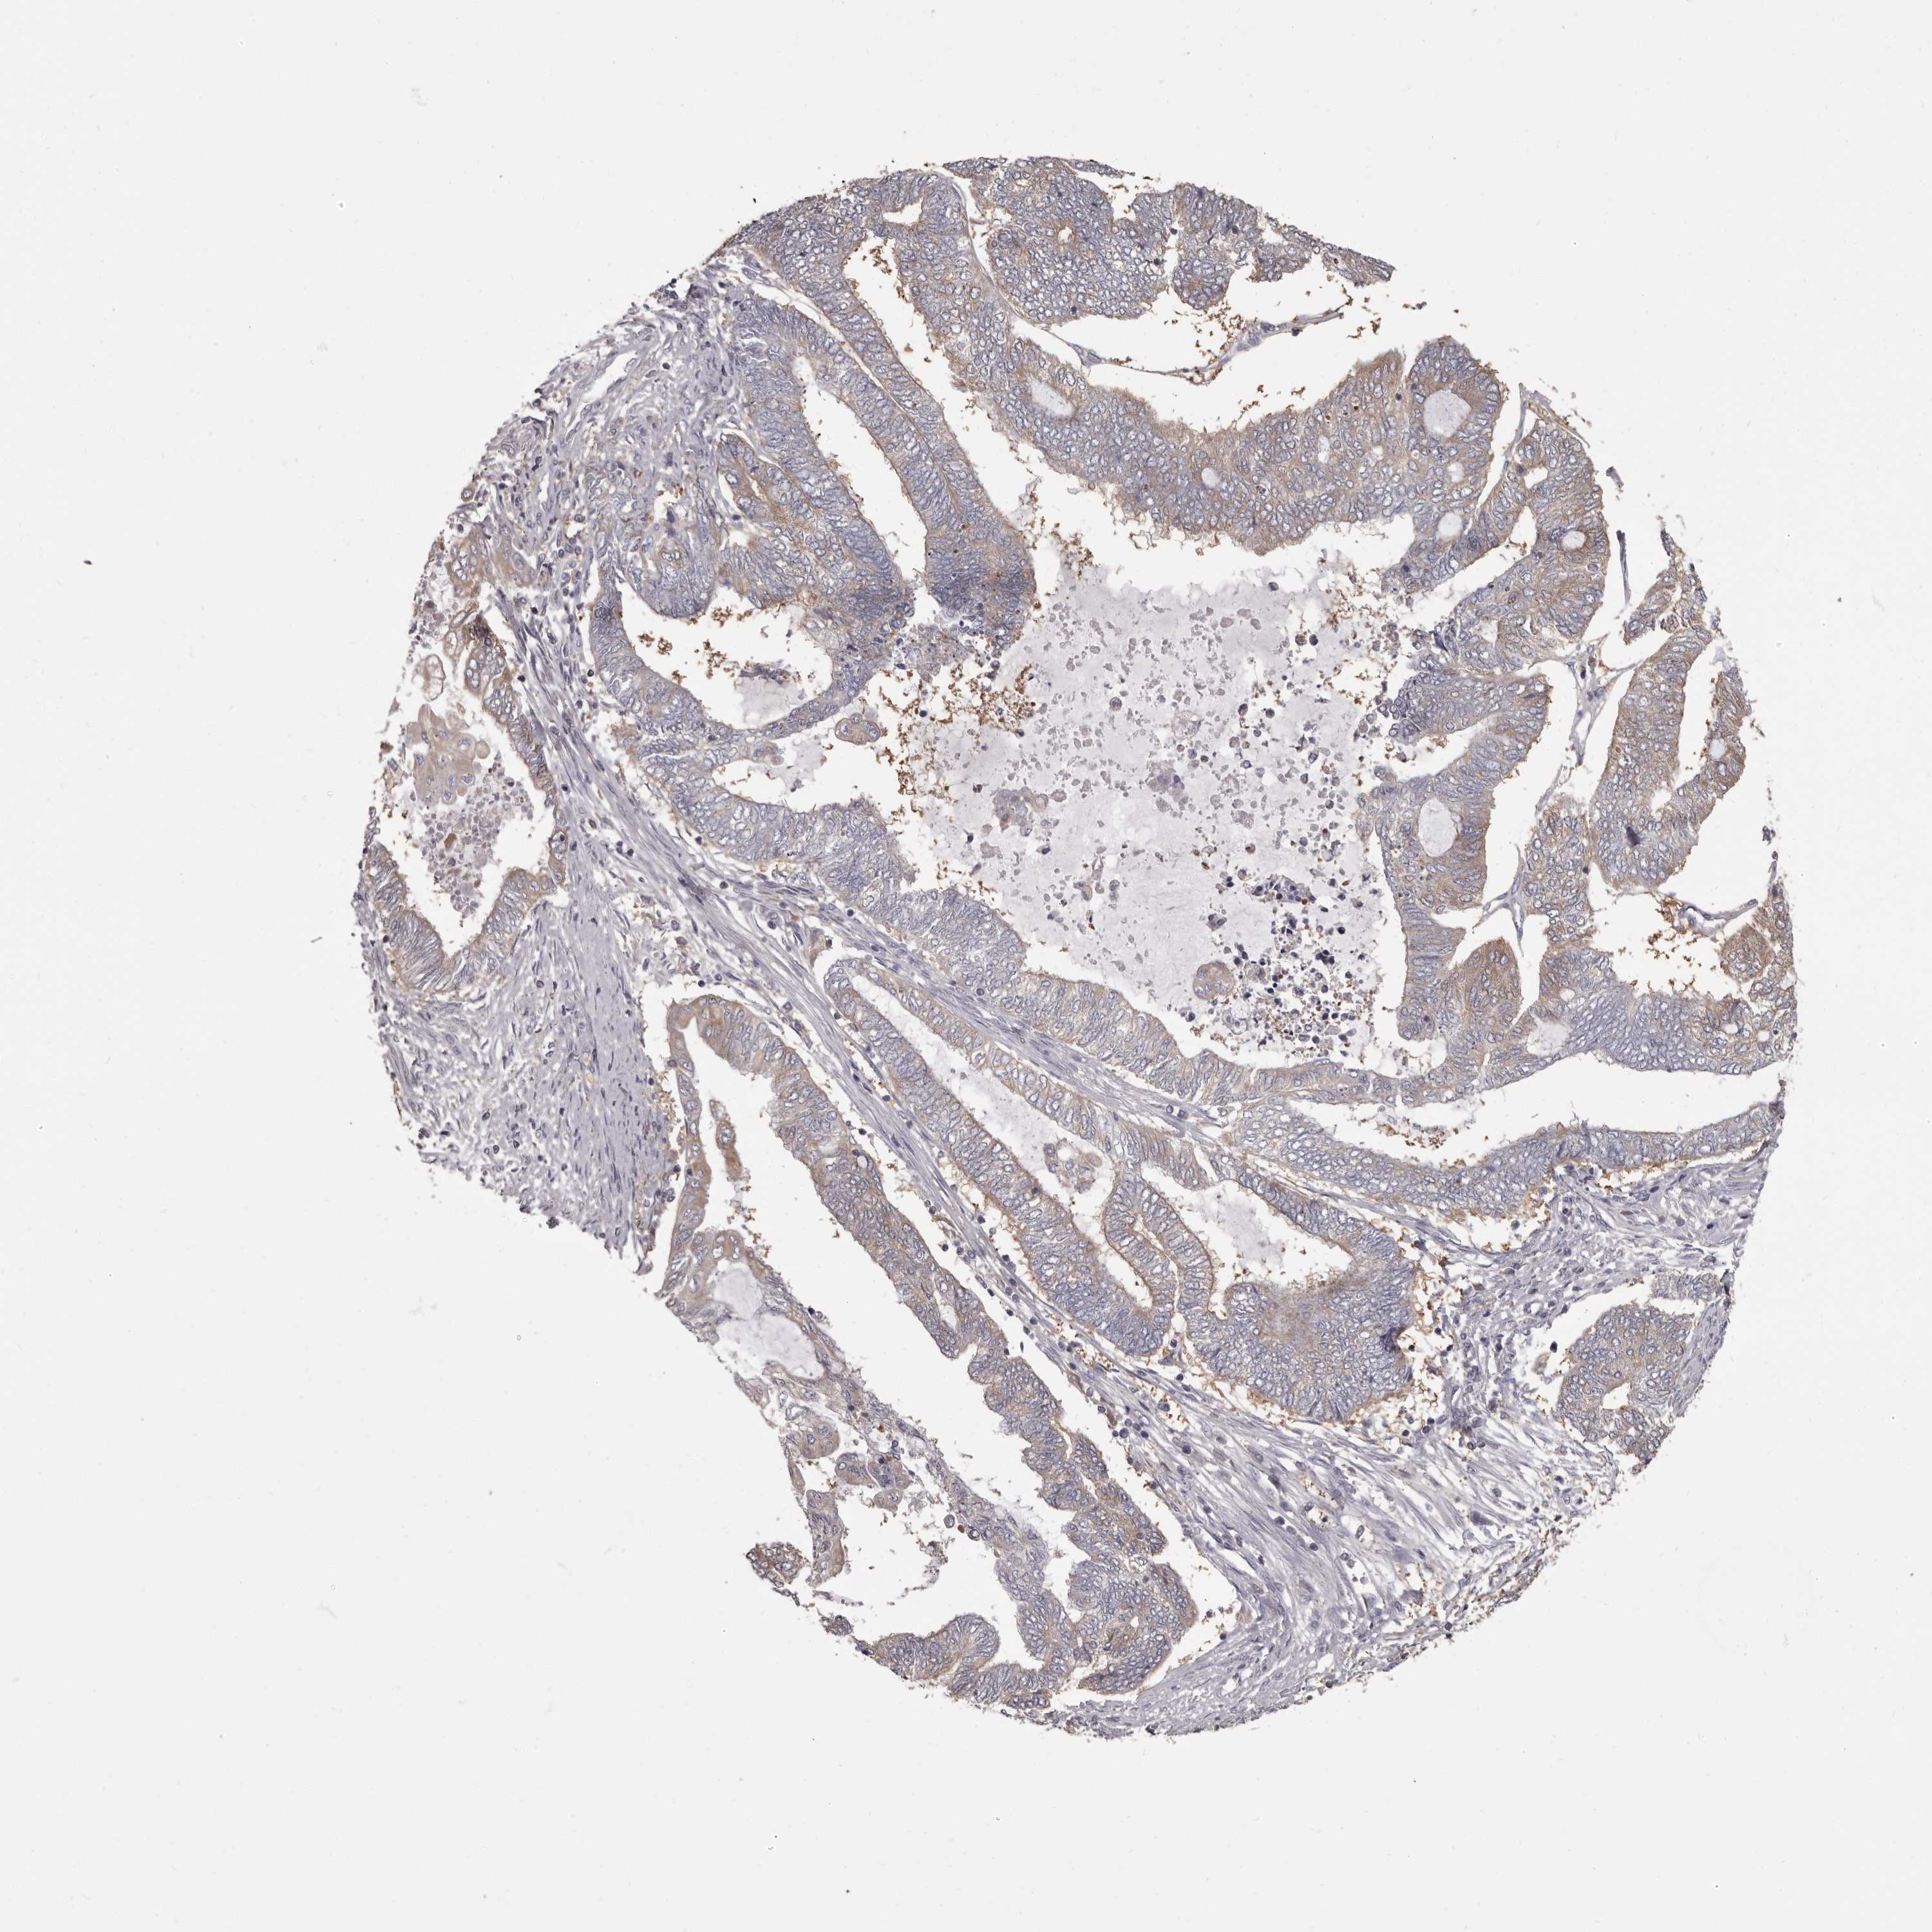

ENDOMETRIAL CANCER - Protein expressioni

A mouse-over function shows sample information and annotation data. Click on an image to view it in a full screen mode. Samples can be filtered based on level of antibody staining by selecting one or several of the following categories: high, medium, low and not detected. The assay and annotation is described here.

Note that samples used for immunohistochemistry by the Human Protein Atlas do not correspond to samples in the TCGA dataset.

Antibody stainingi

Antibody staining in the annotated cell types in the current human tissue is reported as not detected, low, medium, or high, based on conventional immunohistochemistry profiling in selected tissues. This score is based on the combination of the staining intensity and fraction of stained cells.

Each image is clickable and will lead to virtual microscopy that enables deeper exploration of all samples and also displays staining intensity scores, fraction scores and subcellular localization as well as patient and tissue information for each sample.

Antibody HPA029700

Antibody HPA029701

Antibody HPA029702

Antibody HPA029703

Staining

High

Medium

Low

Not detected

Intensity

Strong

Moderate

Weak

Negative

Quantity

>75%

75%-25%

<25%

None

Location

Nuclear

Cytoplasmic/membranous

Cytoplasmic/membranous,nuclear

Adenocarcinoma, NOS

Adenocarcinoma, metastatic, NOS